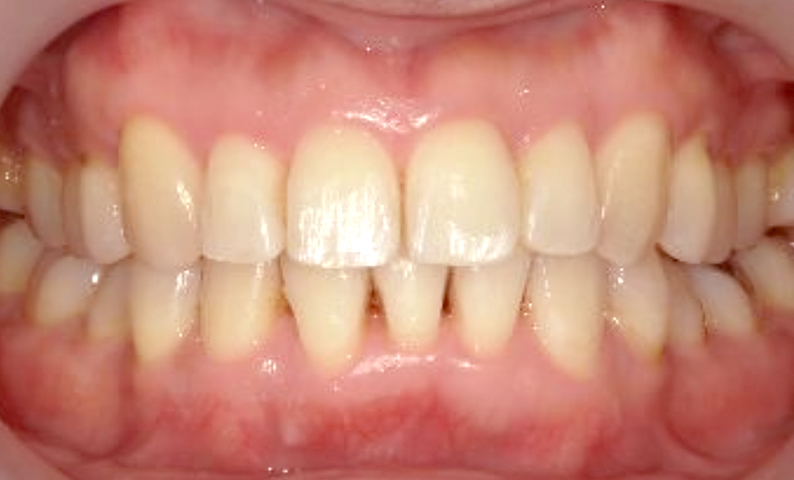

症例_030 上下顎の部分矯正

治療期間:12ヶ月金額:54万円+税女性八の字/V字型捻転歯前歯のガタガタ

| Before | After |

|---|---|

|